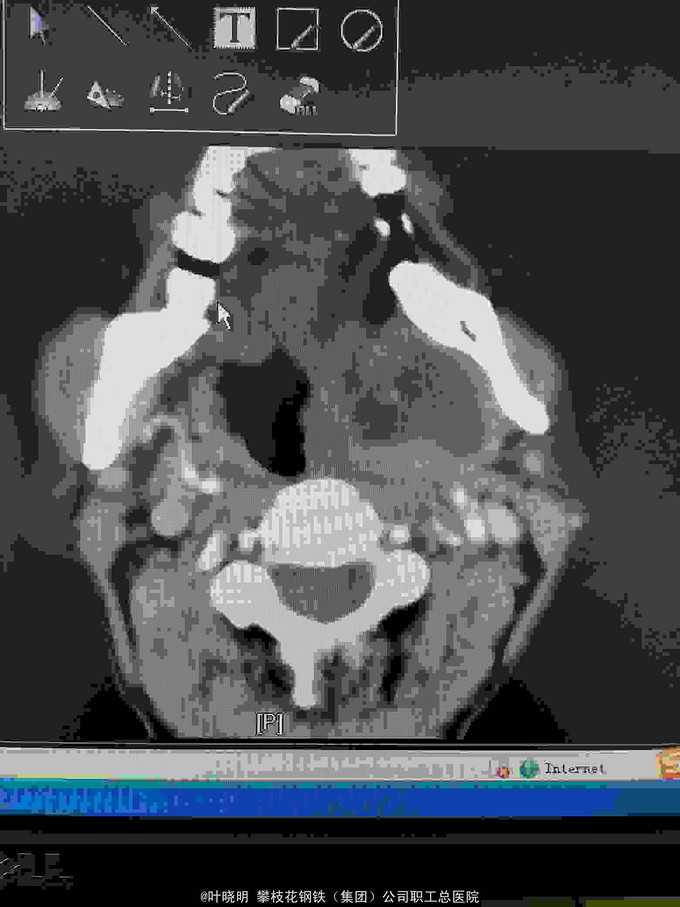

左颌下一4x4.5cm大小包块,质中偏硬突出于皮肤,基底宽,双合诊手感与颌下腺融为一体,穿抽有咖啡色液体。 2016.03.13CT增强示:左颌下区软组识肿块影,密度不均,大小4x5cm,咽喉腔受压变形。考虑为‘’颌下腺肿瘤性病变‘’。